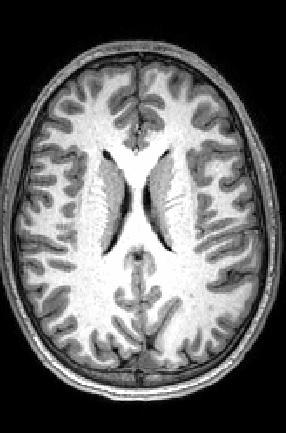

Peterson's team used advanced imaging techniques to acquire two types of information. First, the group used a method called arterial spin labeling, which measures blood flow through the vessels of the brain. Because active parts of the brain need the most oxygen and nutrients, more blood flow to an area signals increased brain activity. Second, the team measured levels of NAA, an amino acid byproduct commonly used as a marker of healthy neurons.

"This is a multimodal imaging data set," explains Peterson, Director of the Institute for the Developing Mind at CHLA and Professor of Pediatrics at the Keck School of Medicine of USC. "Each modality gives us a different window into the brain. We are able to look through both windows at once to tell us much more about what's going on in the brains of these individuals."

Scans revealed a striking pattern in the part of the brain called the white matter.

Our brains have about 100 billion cells, which communicate with each other through long, wire-like branches called axons. These axons are coated with myelin, a specialized wrapping - like wire insulation - that helps the messages flow faster from one cell to another. Because myelin appears white, communication pathways between cells are collectively called white matter . Cell bodies, or gray matter, are not coated as extensively in myelin and therefore do not appear white.